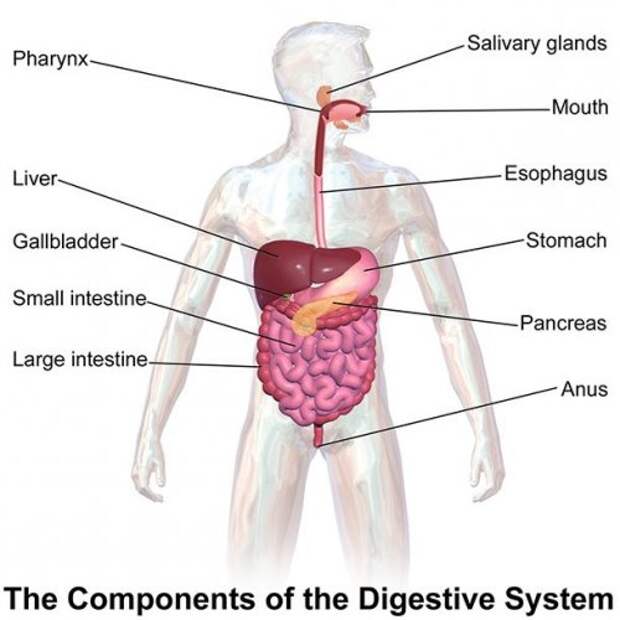

23. Длина всей пищеварительной системы от ротовой полости до ануса составляет почти 9 метров.

Фото: BruceBlaus

23. Длина всей пищеварительной системы от ротовой полости до ануса составляет почти 9 метров.

Фото: BruceBlaus